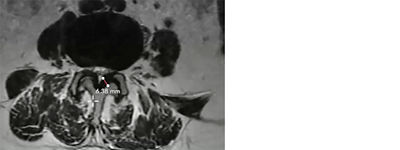

3. Measuring the ligamentum flavum

Using the length tool in the software, I can draw a line across the ligament (the dark area indicated in the image below) to obtain the ligament measurement.

How to measure the ligamentum flavum in a mild® patient

Photo Courtesy of James Lynch, PA – L3/L4 interspace

Here, the measurement clearly shows an HLF of 6.38 mm. I will then repeat this measurement process at each of the levels that are affected by central stenosis (per the report, and as seen in the sagittal view).

As a reminder, any patients with HLF ≥2.5 mm may be considered a candidate for the mild® procedure.4,5